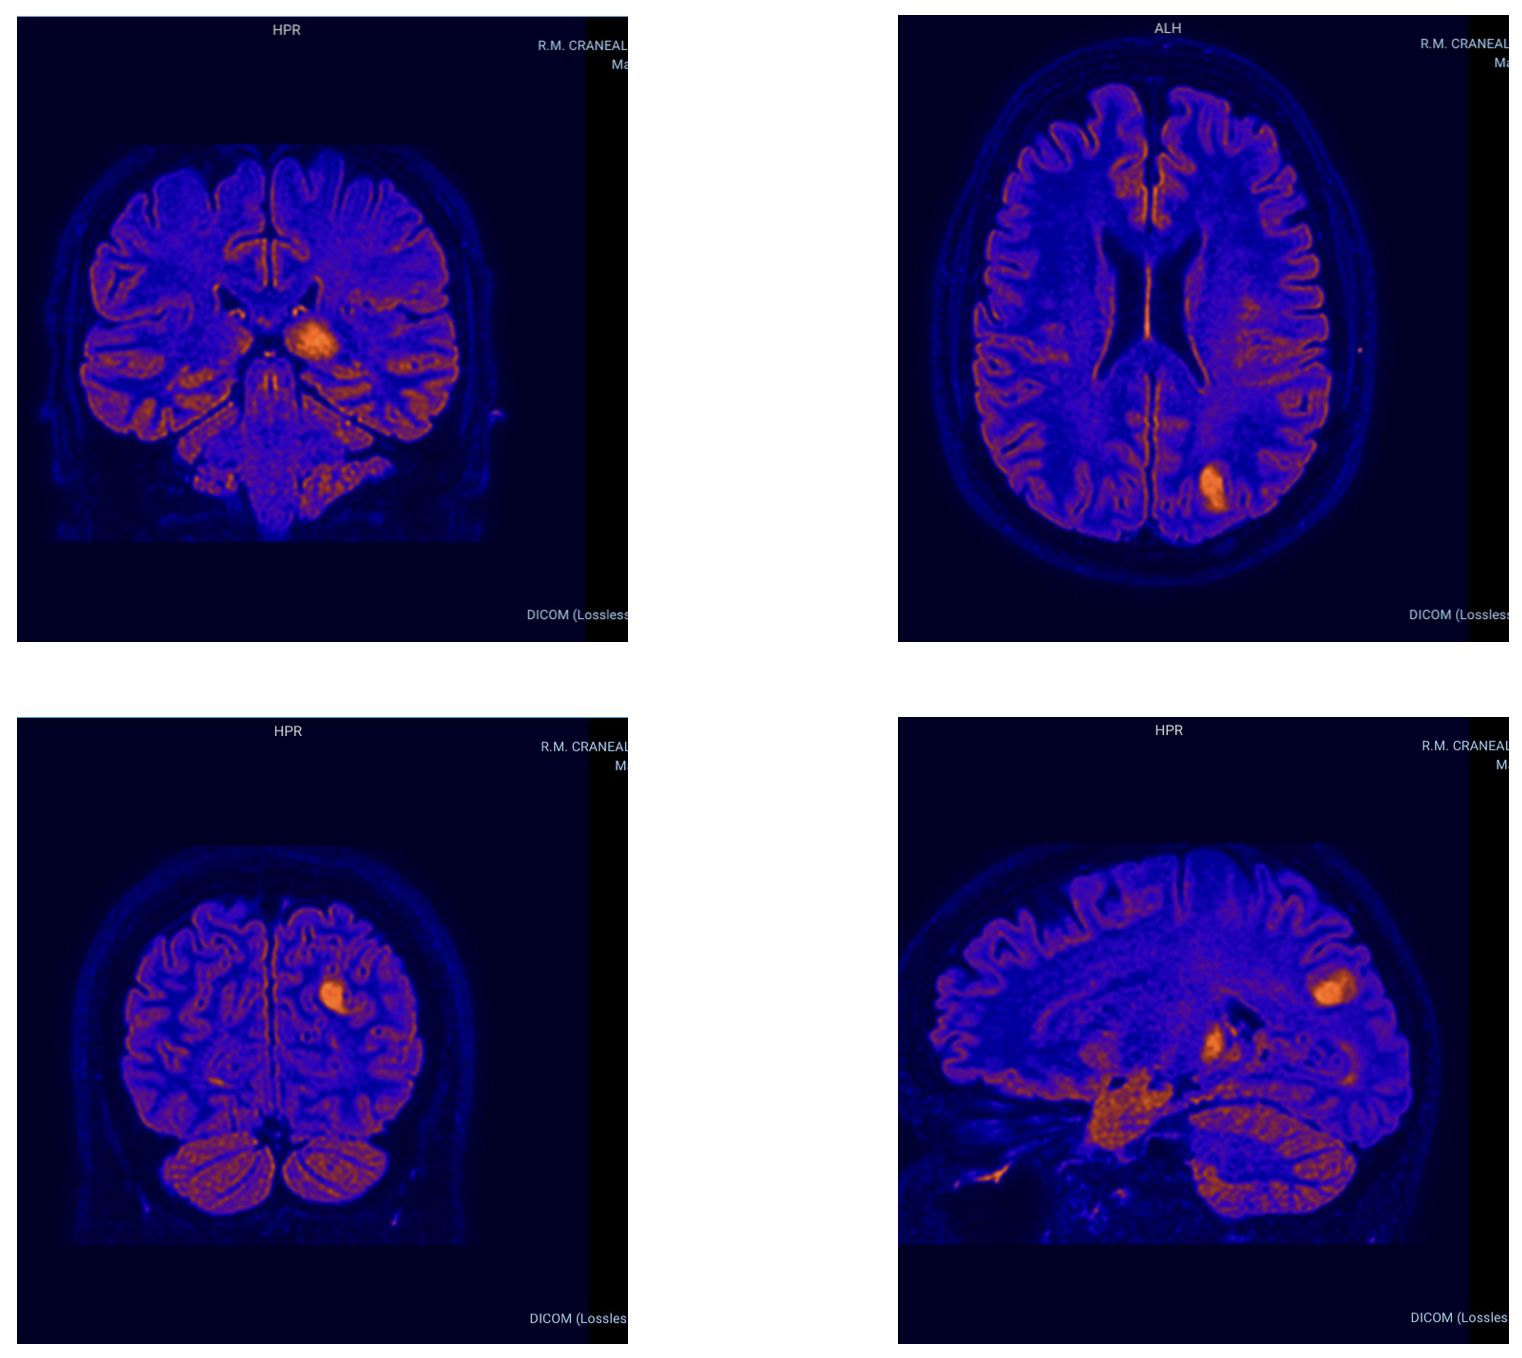

Adjunto el informe de RM cerebral con contraste. La conclusión describe múltiples focos bilaterales, con lesión cortical parietal posterior izquierda con captación en anillo sin restricción de difusión, y plantea como posibilidad una lesión neoplásica glial multifocal con foco de mayor agresividad parietal izquierdo, considerándose menos probable etiología infecciosa o desmielinizante. Solicito derivación preferente a Neurocirugía/Neuro-oncología para valoración de biopsia estereotáxica y planificación de pruebas complementarias (RM avanzada perfusión/espectroscopia o punción lumbar si procede).

Se adjuntan imágenes adicionales similares realizadas en una RMC previa de Febrero de 2026 en el Centro Medico Piramides de Sanitas: